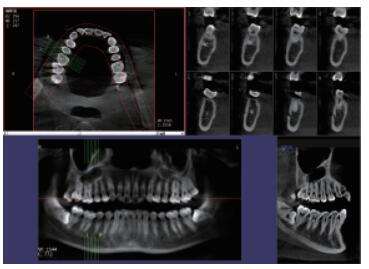

普愛(ài)口腔CT設(shè)備圖像質(zhì)量高產(chǎn)品說(shuō)明:

運(yùn)用口腔CT進(jìn)行檢查可以大大提高口腔科臨床水平。以普愛(ài)醫(yī)療口腔CT為例,(它)可用于口腔種植、正畸、牙體牙髓、牙周、顳下頜關(guān)節(jié)、頜面外科及其他診斷需求,它有掃描速度快、成像速度快、操作軟件專業(yè)性強(qiáng)等優(yōu)點(diǎn),它可以輔助各種臨床診斷與治療。口腔CT產(chǎn)品特點(diǎn):

CMOS成像質(zhì)量?jī)?yōu)

采用高端平板探測(cè)器,分辨率高、圖像質(zhì)量?jī)?yōu)。

三維重建任意斷層

專有三維重建算法,可提供任意位置高清斷層影像。

高清口腔全景影像

通過(guò)三維容積影像,提取高清口腔全景影像。

專有圖像處理軟件

專有圖像校正技術(shù),去除金屬偽影,提高圖像分辨率。

多平面組合重建

可同時(shí)觀察軸向面、冠狀面和矢狀面圖像,方便臨床診斷。